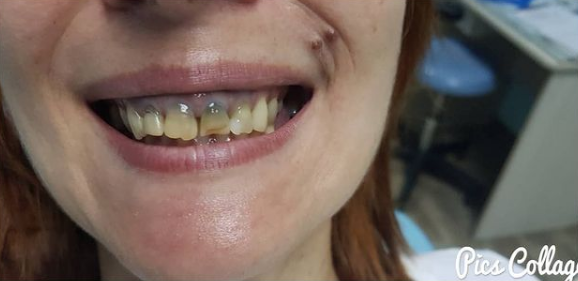

Пациентка, 49 лет. Жалобы частичное отсутствие зубов. Проведено, лечение, удаление несостоятельных зубов, установлены импланты, протезирование коронками из диоксида циркония.